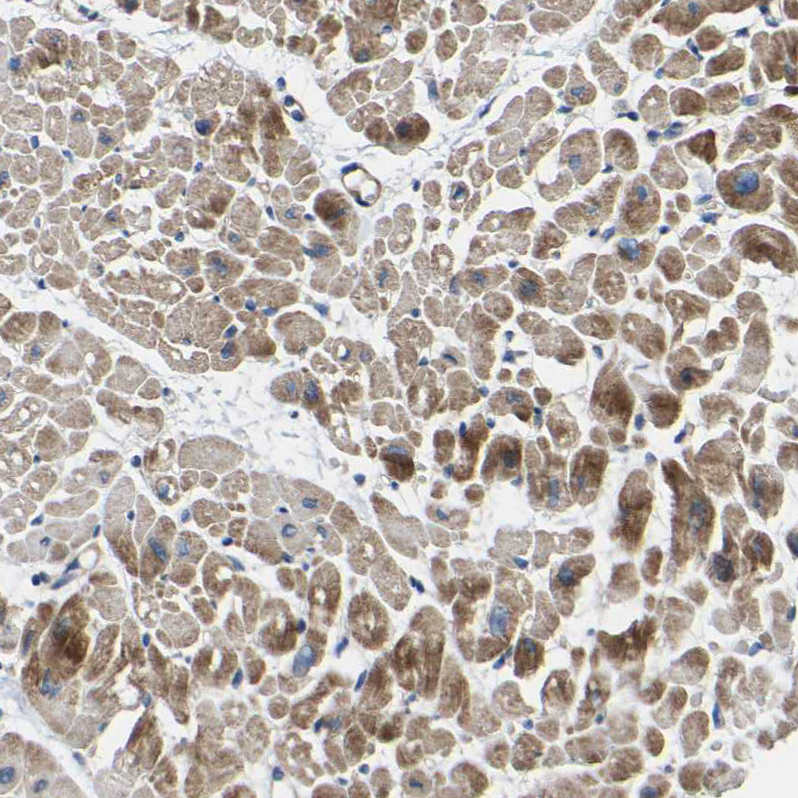

Immunohistochemical staining of human Cerebral cortex shows moderate granular cytoplasmic positivity in neuronal cells.